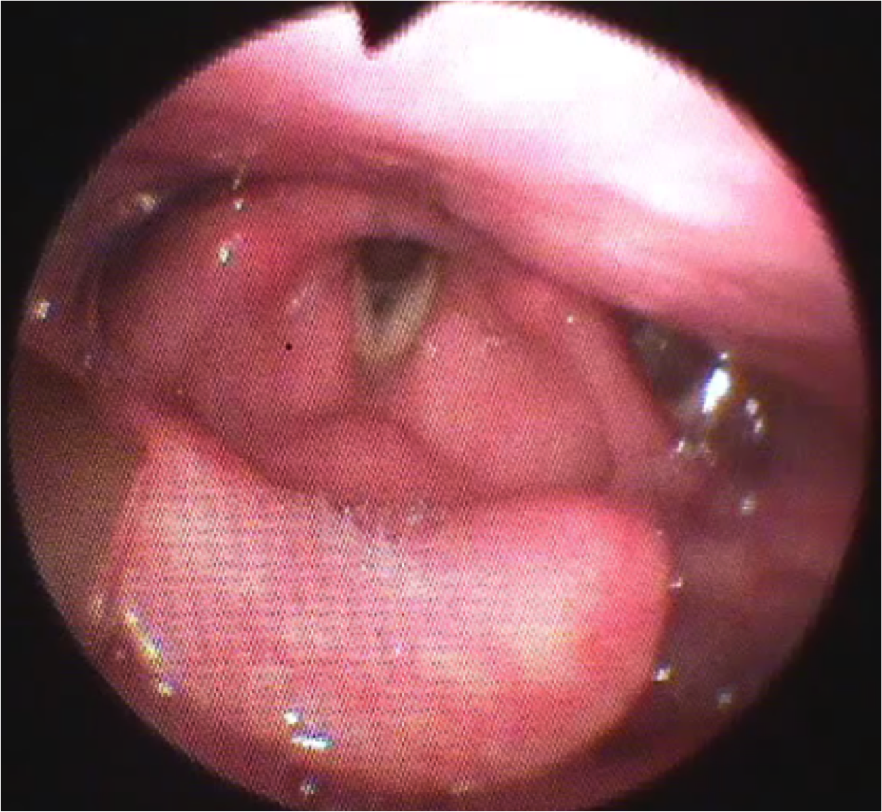

1. 嚥下内視鏡検査(VE)

鼻から細い内視鏡カメラを入れて、のどの様子を直接観察する検査です。のどの中にある痰などの分泌物の存在、のどの動き、食べた物が口からのどに送り込まれる様子を詳しく評価します。